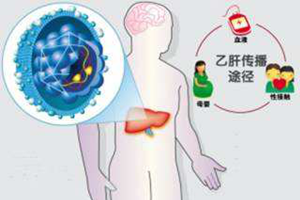

庄辉院士:阻断乙肝母婴传播5要点

庄辉院士:阻断乙肝母婴传播5要点

乙肝病毒表面抗原(HBsAg)阳性母亲生育的新生儿,出生后接受乙肝免疫球蛋白 (HBIG) 和乙肝疫苗联合免疫,母婴传播阻断失败率为5%~10%。

庄辉院士:关于阻断乙肝母婴传播的几个疑问(二)

庄辉院士:关于阻断乙肝母婴传播的几个疑问(二)

HBV母婴传播主要是围生 (产) 期传播,宫内传播的发生率很低。

庄辉院士:关于阻断乙肝母婴传播的几个疑问(一)

庄辉院士:关于阻断乙肝母婴传播的几个疑问(一)

国内外研究均发现,应用替诺福韦酯治疗HBeAg阳性和HBeAg阴性慢性乙肝患者,治疗至12周时,血清HBV DNA水平均降至104IU/ml以下。

目前,儿童的乙肝疫苗接种有标准的免疫程序,但对成年人来说,哪些人需要接种、接种多少剂量、接种几次等,要具体问题具体分析。关键字:乙肝疫苗,接种,成人 庄辉院士:阻断乙肝母婴传播5要点

乙肝病毒表面抗原(HBsAg)阳性母亲生育的新生儿,出生后接受乙肝免疫球蛋白 (HBIG) 和乙肝疫苗联合免疫,母婴传播阻断失败率为5%~10%。关键字:母婴传播,抗病毒药物,乙肝病毒

庄辉院士:阻断乙肝母婴传播5要点

乙肝病毒表面抗原(HBsAg)阳性母亲生育的新生儿,出生后接受乙肝免疫球蛋白 (HBIG) 和乙肝疫苗联合免疫,母婴传播阻断失败率为5%~10%。关键字:母婴传播,抗病毒药物,乙肝病毒 如何预防药物性肝损伤?

HBV母婴传播主要是围生 (产) 期传播,宫内传播的发生率很低。关键字:母婴传播,抗病毒药物,宫内感染

庄辉院士:关于阻断乙肝母婴传播的几个疑问(二)

HBV母婴传播主要是围生 (产) 期传播,宫内传播的发生率很低。关键字:母婴传播,抗病毒药物,宫内感染 耐药耐药,烦得不要不要(二):为啥耐药?(上)

国内外研究均发现,应用替诺福韦酯治疗HBeAg阳性和HBeAg阴性慢性乙肝患者,治疗至12周时,血清HBV DNA水平均降至104IU/ml以下。关键字:妊娠,HBV DNA,母婴传播

庄辉院士:关于阻断乙肝母婴传播的几个疑问(一)

国内外研究均发现,应用替诺福韦酯治疗HBeAg阳性和HBeAg阴性慢性乙肝患者,治疗至12周时,血清HBV DNA水平均降至104IU/ml以下。关键字:妊娠,HBV DNA,母婴传播